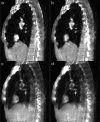

Methods: With the dual-view DTS technique, limited angle scans are performed and projection images are acquired in two orthogonal views: PA and lateral. The dual-view projection data are used together to reconstruct 3D images using the maximum likelihood expectation maximization iterative algorithm. In this study, projection images were simulated or experimentally acquired over 360° using the scanning geometry for cone beam computed tomography (CBCT). While all projections were used to reconstruct CBCT images, selected projections were extracted and used to reconstruct single- and dual-view DTS images for comparison with the CBCT images. For realistic demonstration and comparison, a digital chest phantom derived from clinical CT images was used for the simulation study. An anthropomorphic chest phantom was imaged for the experimental study. The resultant dual-view DTS images were visually compared with the single-view DTS images and CBCT images for the presence of image artifacts and accuracy of CT numbers and anatomy and quantitatively compared with root-mean-square-deviation (RMSD) values computed using the digital chest phantom or the CBCT images as the reference in the simulation and experimental study, respectively. High-contrast wires with vertical, oblique, and horizontal orientations in a PA view plane were also imaged to investigate the spatial resolutions and how the wire signals spread in the PA view and lateral view slice images.

Results: Both the digital phantom images (simulated) and the anthropomorphic phantom images (experimentally generated) demonstrated that the dual-view DTS technique resulted in improved spatial resolution in the depth (PA) direction, more accurate representation of the anatomy, and significantly reduced artifacts. The RMSD values corroborate well with visual observations with substantially lower RMSD values measured for the dual-view DTS images as compared to those measured for the single-view DTS images. The imaging experiment with the high-contrast wires shows that while the vertical and oblique wires could be resolved in the lateral view in both single- and dual-view DTS images, the horizontal wire could only be resolved in the dual-view DTS images. This indicates that with single-view DTS, the wire signals spread liberally to off-fulcrum planes and generated wire shadow there.